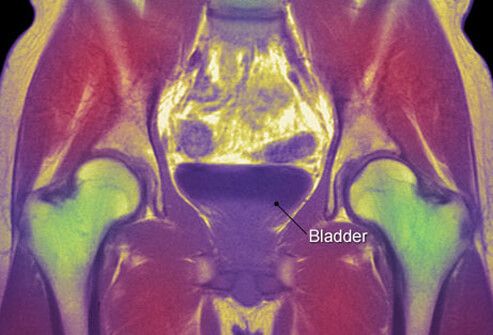

Что показывает МРТ мочевого пузыря

Высокое содержание воды внутри ткани – оптимальный объект для исследования с помощью магнитно-резонансного сканирования, поэтому перед томографией полого мочевого пузыря требуется заполнение жидкостью. За 2 часа до процедуры нельзя ходить в туалет. За этот промежуток выпить 2 литра воды.

Что показывает магнитно-резонансная томография мочевого пузыря:

- Злокачественное перерождение;

- Аномальное строение;

- Воспалительные процессы (цистит);

- Метаплазию – появление в стенке клеток из других отделов мочевого тракта;

- Полипы – патологические выросты внутрь;

- Рубцовое, опухолевое, воспалительное утолщение стенки.